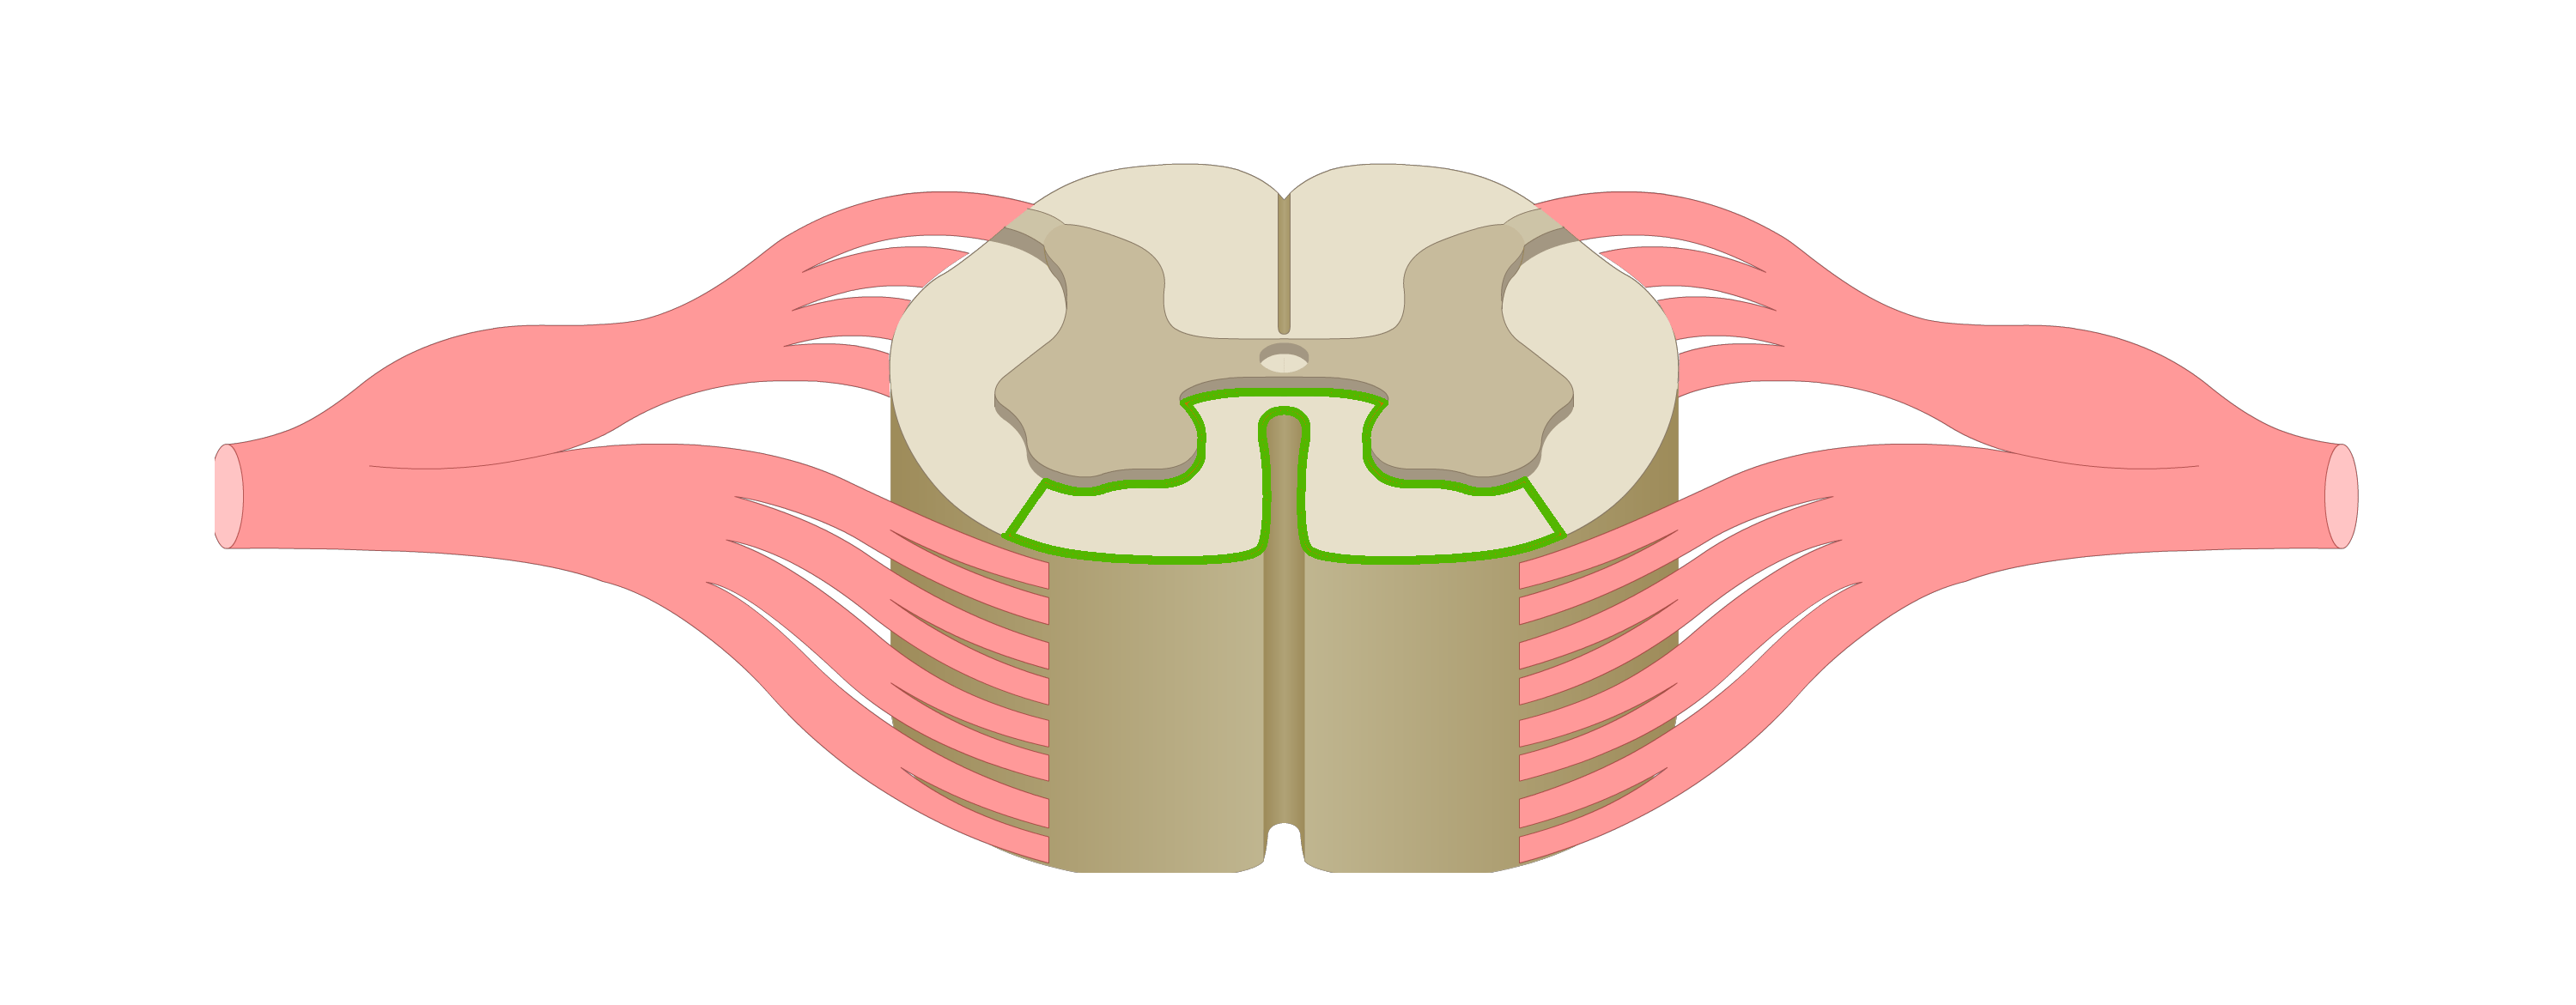

motor tracts

sensory tracts

dorsal root ganglion

dorsal horn

lateral horn

ventral horn

dorsal funiculus

lateral funiculus

ventral funiculus

central canal

ventral median fissure

dorsal median sulcus